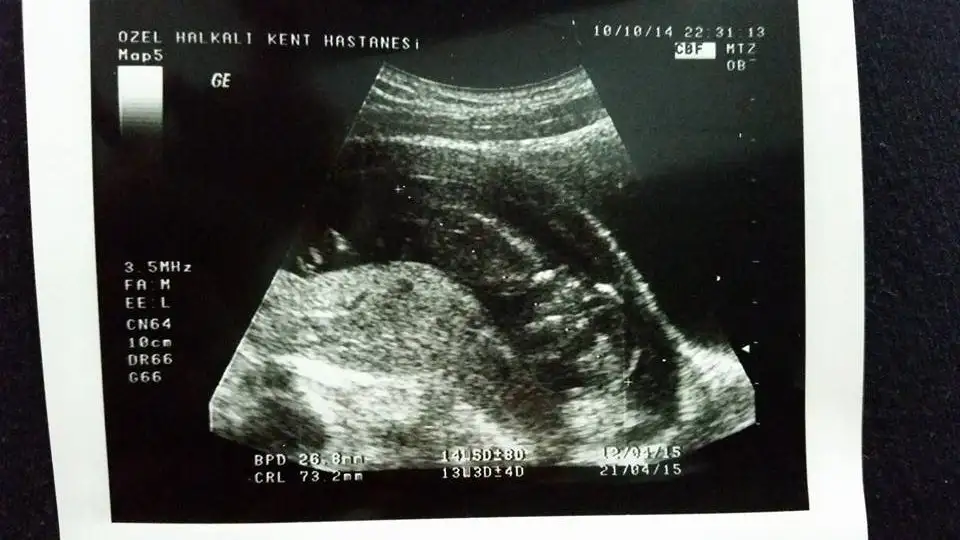

...Banada yorum yaparmisiniz lutfennn 12 haftalik hamileyim bu ultrason görüntüsünde..Eki Görüntüle 1289119